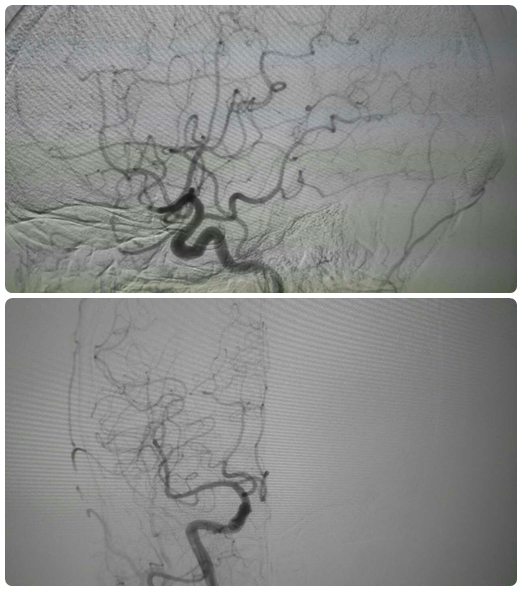

以往对于此类患者,在诊疗的过程中应在心内科做术前检查与准备及评估,择期至导管室行冠脉造影,然后再转至神经内科行术前准备及评估,再择日至导管室行脑血管造影,多次的麻醉、手术、造影为患者带来身体和经济上的双重负担。然而此次,为明确患者是否同时患有心脑血管疾病以及指导下一步治疗,心内三科经过与急诊科的商议,遵从“以患者为中心”的服务理念,决定采用“一站式”联合手术,我院心内三科与急诊科进行学科联合,成功救治了患者吴女士。此类联合手术不仅减少了病人多次麻醉的风险,同时也降低了近三分之一的医疗费用。据悉,这是我院首例采用联合手术治疗高危疑难心血管疾病的病例。

心内三科主治医生郑崔成介绍,外科手术和介入是治疗心脑血管疾病最为常见的两种手段,联合手术融合了外科及介入治疗的技术优势,在治疗冠心病、先天性心脏病、瓣膜心脏病等血管疾病时具有直观性、操作容易、方便定位、手术切口小、术后恢复快等优势。随着医学影像学设备和介入治疗器械的发展与成熟,联合手术成为治疗复杂疑难心血管疾病的发展方向。行此次联合手术的急诊科医生鄂永军也表示“一站式”联合手术可以一次性解决患者手术问题,无需在内科和外科间多次转移患者,从而避免多次麻醉和转运带来的风险。急诊科的工作忙碌、压力大,但鄂永军医生依旧挤出时间不断钻研专业知识,希望能在专业领域有进一步的提升,能为患者带来更高效优质的诊疗服务。